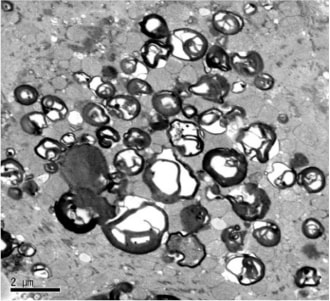

心アミロイドーシスでは、アミロイドという繊維質のような物質が心筋に沈着し、心肥大(壁肥厚)に伴う心不全や不整脈を併発する疾患です。アミロイドの前駆体がトランスサイレチンであるタイプ(ATTRアミロイドーシス:変異型ATTRvと野生型ATTRwtに分かれます)と前駆体が免疫グロブリン軽鎖であるALアミロイドーシスがあります。高齢者で良く見られるATTRwtの診断は心筋の壁肥厚や、心筋生検におけるアミロイド・前駆体沈着や核医学検査(99mTc-ピロリン酸シンチまたは99mTc-HMDPシンチ)などが有用です。

99mTc-HMDPシンチで心臓に集積がみられます。